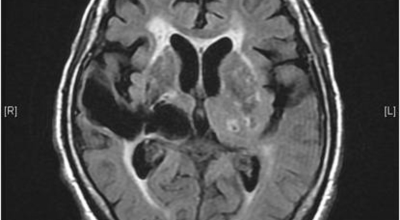

뇌출혈이란 뇌혈관의 출혈이 원인이 되어 일어나는 뇌혈관장애, 뇌일혈이라고도 그러나, 이는 갑작스러운 의식 장애, 이완성 반신불수 등을 유발하는 뇌졸중을 유발하는 대표적인 질환이예요. 뇌출혈의 대부분의 원인은 고혈압증이 원인이지만 드물게 백혈병이나 재생불량성 빈혈 과 같은 혈액질환과 함께 종양, 외상, 매독 등이 원인이 됩니다.

고혈압성 뇌출혈의 원인은 고혈압만이 아니라 터지기 쉬운 상태의 혈관에도 있다고 생각이 가능하지만, 아직까지 발생병리는 완전히 해명이 되지 않은 상태예요. 현재 생각 되는 것은 뇌내세 소동맥, 보통과 다르게 분기부의 혈관벽에 변화가 일어나서 연약해진 곳이 내압을 이겨내지 못하고 팽배해서 터져서 출혈을 한다는 것이죠. 뇌출혈이 일어나는 장소는 내포 부근이 가장 많다고 하며 이 부분의 중대뇌동맥의 가지가 터져서 출혈해요.

뇌출혈은 발작 직후 안정을 취해야 해요. 뇌부기를 가라앉히기 위해 약물 요법으로 고농도 포도당, 덱사메타존, 만니톨 등을 투약할 수 있고 뇌의 혈액 순환을 회복시키는 주사와 지혈제, 진정제 등을 활용할 수 있답니다. 혈종의 크기가 중등도 이상으로 마비 증세가 있다면 머리뼈에 작은 구멍을 내서 관을 넣어 혈종을 뽑아내는 수술을 시행할 수 있습니다.

혈압성 뇌출혈인 경우 혈종의 크기가 작으며 환자의 증상이 경미하면 약물 치료를 시행해요. 혈종의 크기가 아주 크며 뇌가 심하게 부어오를 때는 응급으로 머리뼈를 절개해 혈종을 빠르게 제거해야해요. 응급조치가 늦어지면 뇌압이 상승해 의식을 잃고 사망에 이를 수 있기 때문인데요 이렇게 증상이 심할 때는 수술이 잘 되었더라도 예후가 좋지 못할 때가 많다고 해요.